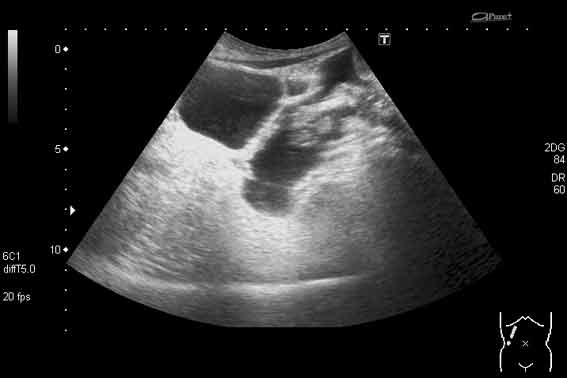

Да, трихобезоар.

Вложения

4.jpg

5.jpg

6.jpg